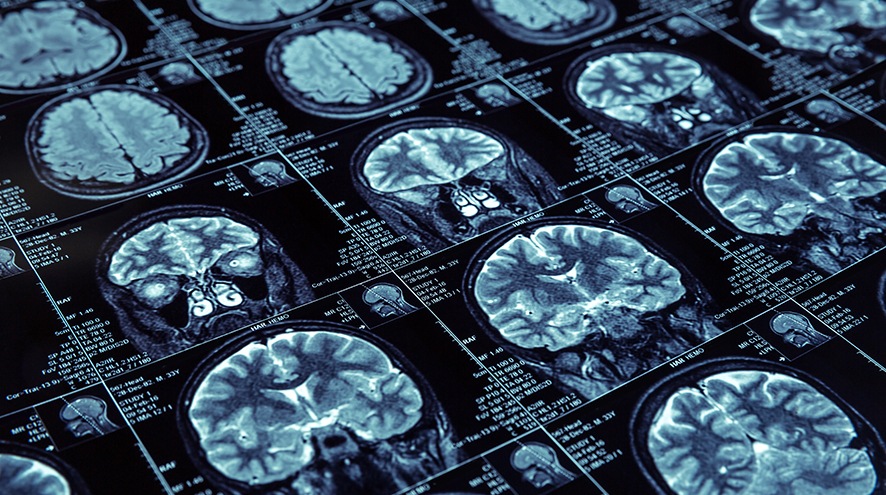

There is no simple test for Alzheimer’s disease and other dementias. But there is research ongoing that is looking at newer, better ways to detect dementia earlier and quicker, before the symptoms become apparent. But right now, a combination of memory tests and scans are required.